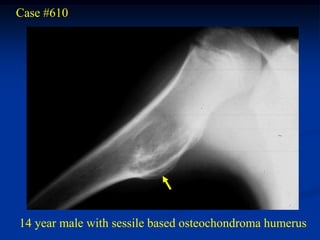

Case #610

14 year male with sessile based osteochondroma humerus

Bone scan

Coronal T-1 MRI

Cut surgical

specimen

cap

cartilage cap

Photomic